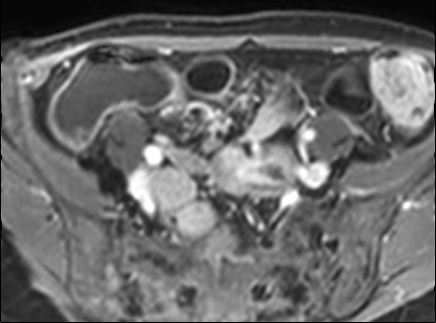

Bệnh nhân nữ 48 tuổi, đang điều trị bằng thuốc kháng TNF, được chỉ định nội soi đại tràng.

Phát hiện hẹp lòng ruột ở đại tràng sigma, không thể vượt qua được khi nội soi.

MR-enterography được thực hiện để đánh giá mức độ lan rộng của chỗ hẹp.

Ruột non bình thường, nhưng ghi nhận các đoạn hẹp ở đại tràng xuống và đại tràng ngang.

Cả hai đoạn hẹp đều có thành ruột dày đến 8 mm và ngấm thuốc rõ rệt theo kiểu niêm mạc ở đại tràng xuống và kiểu phân lớp ở đại tràng ngang.

Giãn ruột trước chỗ hẹp được ghi nhận ở cả hai đoạn.

Do các chỗ hẹp này không hiện diện khi nội soi đại tràng trước khi điều trị kháng TNF, nhiều khả năng chúng đã hình thành trong quá trình điều trị.

Do đó, quyết định phẫu thuật cắt đại tràng gần toàn bộ với miệng nối hồi-sigma đã được đưa ra.